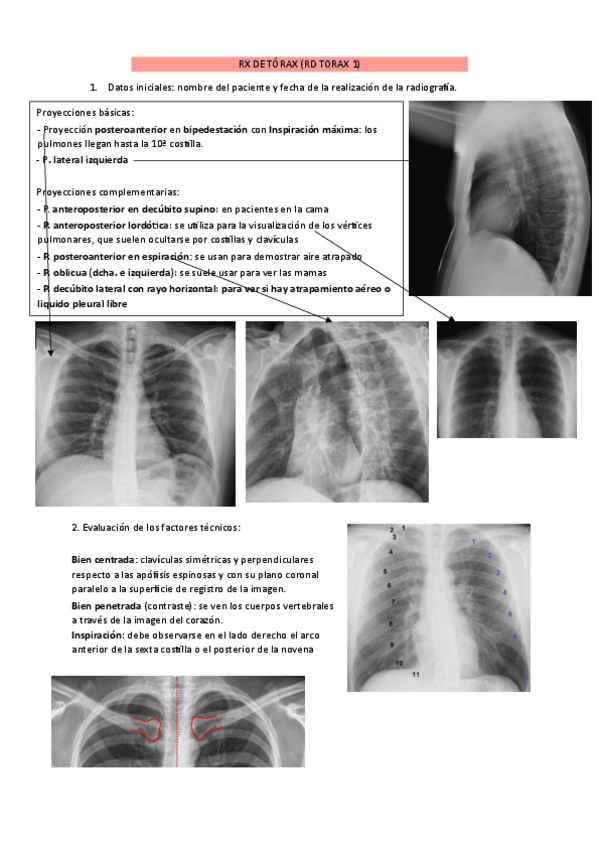

He publicado nuevos apuntes de 3º Radiología: interpretar-radiografia-de-torax.pdf

15 páginas